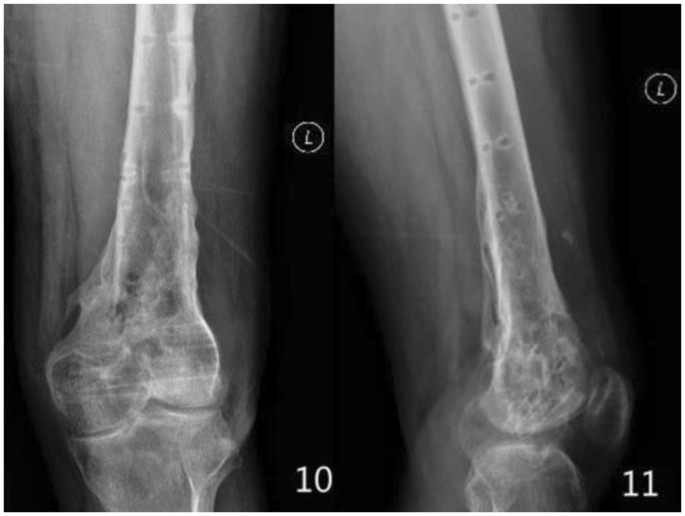

All patients were followed up for 12 to 48 months. The follow-up records of one patient of the double-plate group are shown in Figs 1–5 and those of one patient of the single plate group are shown in Figs 6 and 7. One patient in each group died one year and a half after the operation due to other causes. There were 58 patients and 60 cases of distal femoral fractures in total, of which one patient had bilateral distal femoral fractures both fixed by lateral plate and the other one with bilateral distal femoral fractures had a single plate on the right distal femur and double plates on the left. The age distribution of patients in the single-plate group and the double-plate group is shown in Table 1. There was no significant difference between the two groups (p = 0.330).

Inclusion criteria: Patients with distal femoral fractures treated with locking plate(s). Exclusion criteria: Patient with a decline of muscle strength of lower extremities. Anterior-Posterior and lateral plain film, computed tomography and 3D reconstruction of the fracture sites were performed to identify the fracture types.